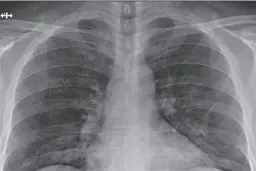

مشکلات ریه در کرونا؛ از علائم تا درمان

یک فوق تخصص جراحی قفسه سینه گفت: علائم درگیری ریه در کرونا…